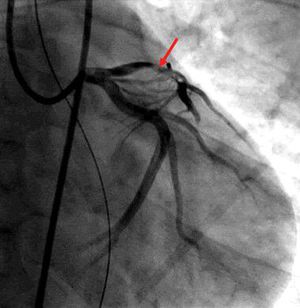

Introduction The appearance of MI under the age of 40 is rare but the lack of thermodynamically significant coronary artery disease in this age group is not so uncommon since 15-20% of these patients has normal or near normal coronary arteries (N/NNCAs). It is associated with devastating consequences because of the extensive damage that accompanies its abrupt occurrence and absence of collateral coronary circulation. The diagnosis and appropriate management of the underlying cause are essential in preventing recurrence. Other than the traditional risk factors for atherosclerosis, a variety of potential contributing factors have been identified in young patients with myocardial infarction. These include the use of oral contraceptives in young women, cocaine use, marijuana use, a factor V Leiden mutation and protein C deficiency Case Presentation A 33 year old male with a past medical history of protein C and S deficiency, pulmonary embolism and tobacco use who presented to the emergency department for witnessed sudden cardiac arrest proceeded by chest pain while ambulating at home then developed a seizure like activity. He has a family history of clotting disorder in his mother who was diagnosed with a deep venous thrombosis and brother who experienced a myocardial infraction in his 30s. He consumes approximately half-pack/day of cigarettes with occasional alcohol and marijuana use. He was diagnosed with pulmonary embolism and protein C and S deficiencies in 2007 treated with Warfarin for 6 months then declined to continue indefinite systemic anticoagulation for the past eight years. Upon arrival of EMS, he found to have agonal breathing and posturing with cardiac monitor demonstrating a disorganized rhythm consistent with ventricular fibrillation in which advanced cardiovascular life support (ACLS) protocol was immediately initiated, received one round of defibrillation of 200 joules and was subsequently transferred to the emergency department. En route, had two more episodes of ventricular fibrillation with two rounds of successful defibrillation at 200 J. He was intubated for airway protection. Physical examination showed an unresponsive intubated male with heart rate of 74 beats per minute, blood pressure of 123/67 mm Hg, saturating at 100% with supplemental oxygen on 50% and S 3 was heard on auscultation without evidence of volume overload. Initial laboratory work up showed troponin levels of 0.03 ng/ ml then peaked at 15.61 ng/ml and leukocytosis of 21,100 k/μl. Urine drug scree was negative. An electrocardiogram (ECG) showed an acute anterolateral ST segment elevation .He immediately underwent a coronary angiography showing a significant thrombus burden in proximal LAD, had successful angiojet thrombectomy with ST segment elevation resolution . He was admitted to the cardiac intensive care unit on therapeutic intravenous Heparin and Tirofiban infusion. Initial transthoracic echocardiogram (TTE) showed a depressed left ventricular ejection fraction (LVEF) of 30% with left ventricular regional systolic dysfunction in the LAD territories. TTE was repeated in 24 h after thrombectomy and exhibited an improved LVEF to 55%. He remains stable and was discharged with continuation of systemic anticoagulation with warfarin with INR goal 2-3, beta blocker, Aspirin, Ticagrelor and Statin. Discussion Acute coronary syndrome in young adults is an uncommon condition; only 2-8% of acute myocardial infarction subjects are under 40 years’ old [6,7]. Males are typically more affected, females account for only 6% in this age group [8].The mean cause of acute coronary syndrome in the young is atherosclerosis; numerous factors can lead to premature and accelerating process such as insulin resistance, diabetes, familial lipid disorder, hypertension, tobacco use, and human immunodeficiency virus infection [9]. Acute coronary syndromes may have non-atherosclerotic etiologies: Congenital coronary artery anomalies, spontaneous coronary artery dissection, vasospasm, illicit drug use and hypercoagulable states like our case. In the absence of coronary disease, the clinicians should expand the differential towards an inherited thrombophilia especially in young individuals presenting with acute coronary syndrome. The inherited thrombophilia syndromes involve several disorders including protein C deficiency, protein S deficiency, hyperhomocysteinemia, with factor V Leiden deficiency having the highest prevalence. Individual case reports on protein C and S deficiencies have been published about the consequences of arterial thrombosis resulting in myocardial infarction which is known to be a rare manifestation of these conditions. A recent work with 255 consecutive patients who had survived a STEMI ≤ 35 years of age reported that only one had deficiency of protein C (0.4%) (10) The role of protein C and S inactivates clothing factors Va and VIIa towards the formation of thrombin. In their absence, individuals have a severely higher risk for developing venous thrombosis and pulmonary embolism. Because patients with previous venous thrombosis, also have had arterial thrombosis, there have been studies to establish whether patients with thrombophilia and antecedents of venous thromboembolisms have a higher risk of arterial thrombosis [11,12]. One study included 1081 consecutive patients (649 Female/432 Males, age range 16-93) registered with venous thromboembolism in MAISTHRO database (Main-Isar-Thrombosis). Thrombophilia screening tested the presence of factor Ⅴ Leiden, G20210A prothrombin gene mutation, antiphospholipid antibodies, factor VII, protein C, protein S and antithrombin activities. From all of the patients, 40 (3.7%) had a prior myocardial infarction (MI) and 41 (3.8%) had a stroke. Only the presence of lupus anticoagulant was found statistically significant. The conclusion was that the cumulative incidence of arterial thrombotic events is low for those with antecedents of venous thrombosis and inherited thrombophilia doesn’t seem to substantially increase the risk of arterial thrombosis [13]. Another study that included members of protein C, S and antithrombin deficient families also proved that subjects with previous venous thrombosis had a similar risk for arterial thrombosis as those without antecedents of venous thrombosis, so there seems to be no association between venous thrombosis and the subsequent arterial thrombosis [14]. Only some studies and case reports have discussed the implication of trombophilic defects in arterial thrombosis. The results are controversial. In one cohort family study, the arterial events were diagnosed in 8% of the 144 subjects with protein C or S deficiencies and 1% from the 94 subjects with antithrombin deficiency [15]. In another ample study on carriers of familial thrombophilia (the European Prospective Cohort on Thrombophilia [EPCOT] study), overall annual incidences of myocardial infarction and/or ischemic stroke after 20 years of age were 0.15%, 0.18Z% and 0.15% in subjects with protein S (n=111), protein C, (n=150), and antithrombin deficiency (n=92), respectively [16]. A more recent study reported annual incidences of myocardial infarction and/or ischemic stroke of 0.32% (protein S), 0.32% (protein C) and 0.21% (antithrombin) in deficient subjects and 0.19% in non–deficient subjects >20 years of age [17]. In a case-control study, arterial thrombosis was recorded more frequently in 88 cases with protein S, protein C, or antithrombin deficiency (19% arterial thrombosis) compared with control subjects with venous thromboembolism without these deficiencies (1% arterial thrombosis) [17]. Lifelong systemic anticoagulation is the recommended treatment with emphasis of initiation towards symptomatic patients. The potential long term morbidity in young individuals must be recognized when discussing the long term risk and benefits of systemic anticoagulation. This case report highlights that the diagnosis of protein C and S deficiency in young patients with myocardial infarction is essential for more appropriate management and prevention of recurrent events. Furthermore, family screening could lead to a prophylactic approach in carriers of this mutation. Patients and affected family members need to be informed of the risks, signs, and symptoms of thrombosis and the importance of prophylactic strategies. Education and counseling of the patient’s carrier status may also impact decisions about the indication of antithrombotic prophylaxis. Conclusion Hypercoagulable state caused by protein C and S deficiency without appropriate anticoagulant therapy can cause acute myocardial infarction in young adults with normal coronaries and without any underlying major risk factors for coronary artery disease. Raising patient awareness is paramount. Family screening could prevent catastrophic cardiovascular events.